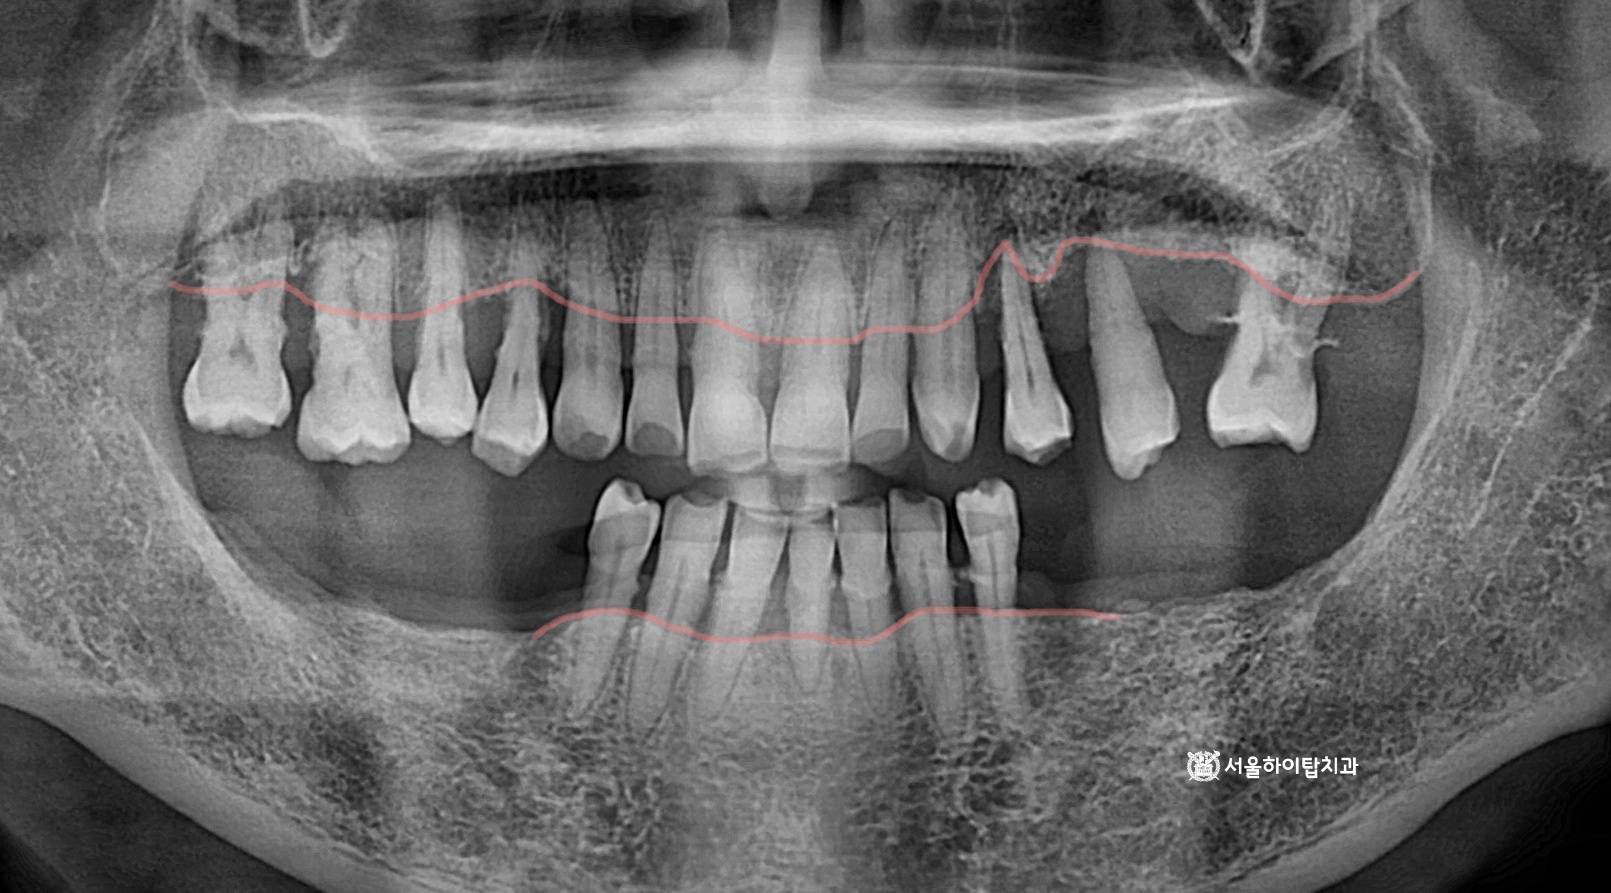

동암역 치과 : 균형 잡힌 저작이 중요한 이유, 전반적으로 손상된 치아 및 잇몸 임플란트를 통해 저작 기능 개선 간석역 치과 치주염으로 인한 치조골 흡수, 치아 파절 및 마모까지 임플란트 가상 시뮬레이션을 통한 안전한 수술 과정 1 2 Next